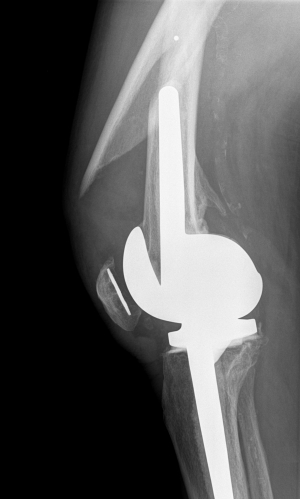

Standard AP and lateral views are the basis of fracture analysis and classification. Typical signs of loosening like displacement of the femoral component or stem from the distal femur or separation of cement can be seen in the X-ray. Nevertheless in difficult cases a CT-scan can be helpful in order to detect loosening around the femoral component.